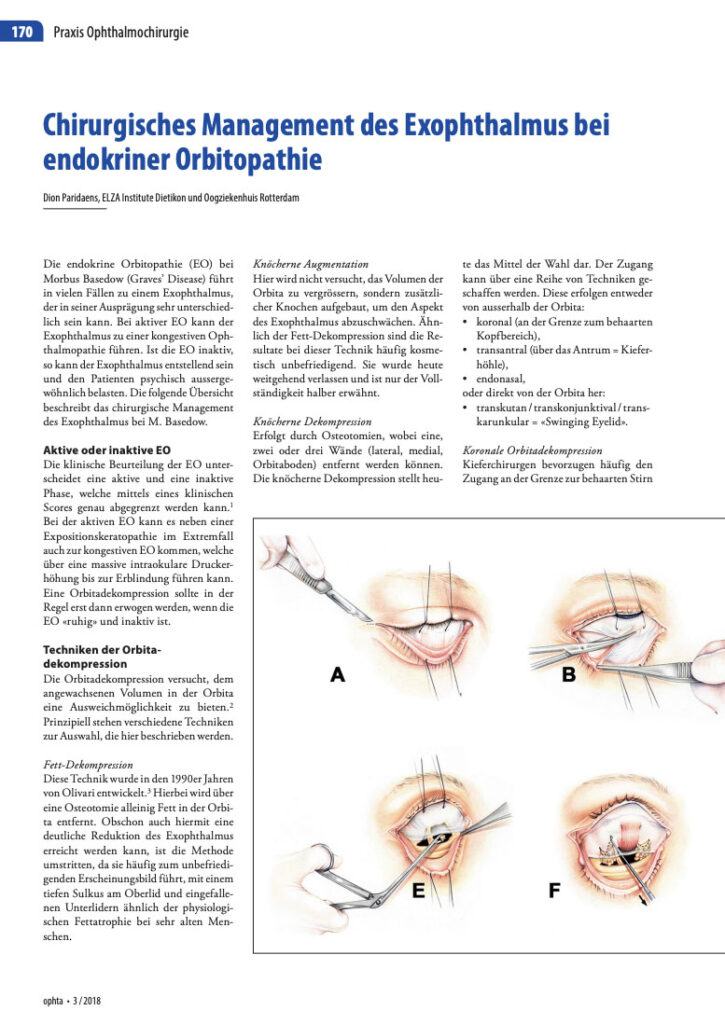

Surgical correction with orbital decompression

Once the inflammatory phase has stabilized, orbital decompression surgery can restore the natural position of the eyes. During this operation, small sections of orbital bone and, when needed, excess orbital fat are removed to relieve pressure and create space within the orbit. The eye then settles backward into a more normal alignment, improving both function and appearance.

He specializes in the transconjunctival (swinging-eyelid) approach, which allows access to the orbit through the inside of the eyelid—leaving no external scars. This minimally invasive technique provides excellent visualization of the orbital walls, precise bone removal, and controlled decompression, while preserving critical support structures to minimize the risk of postoperative double vision.